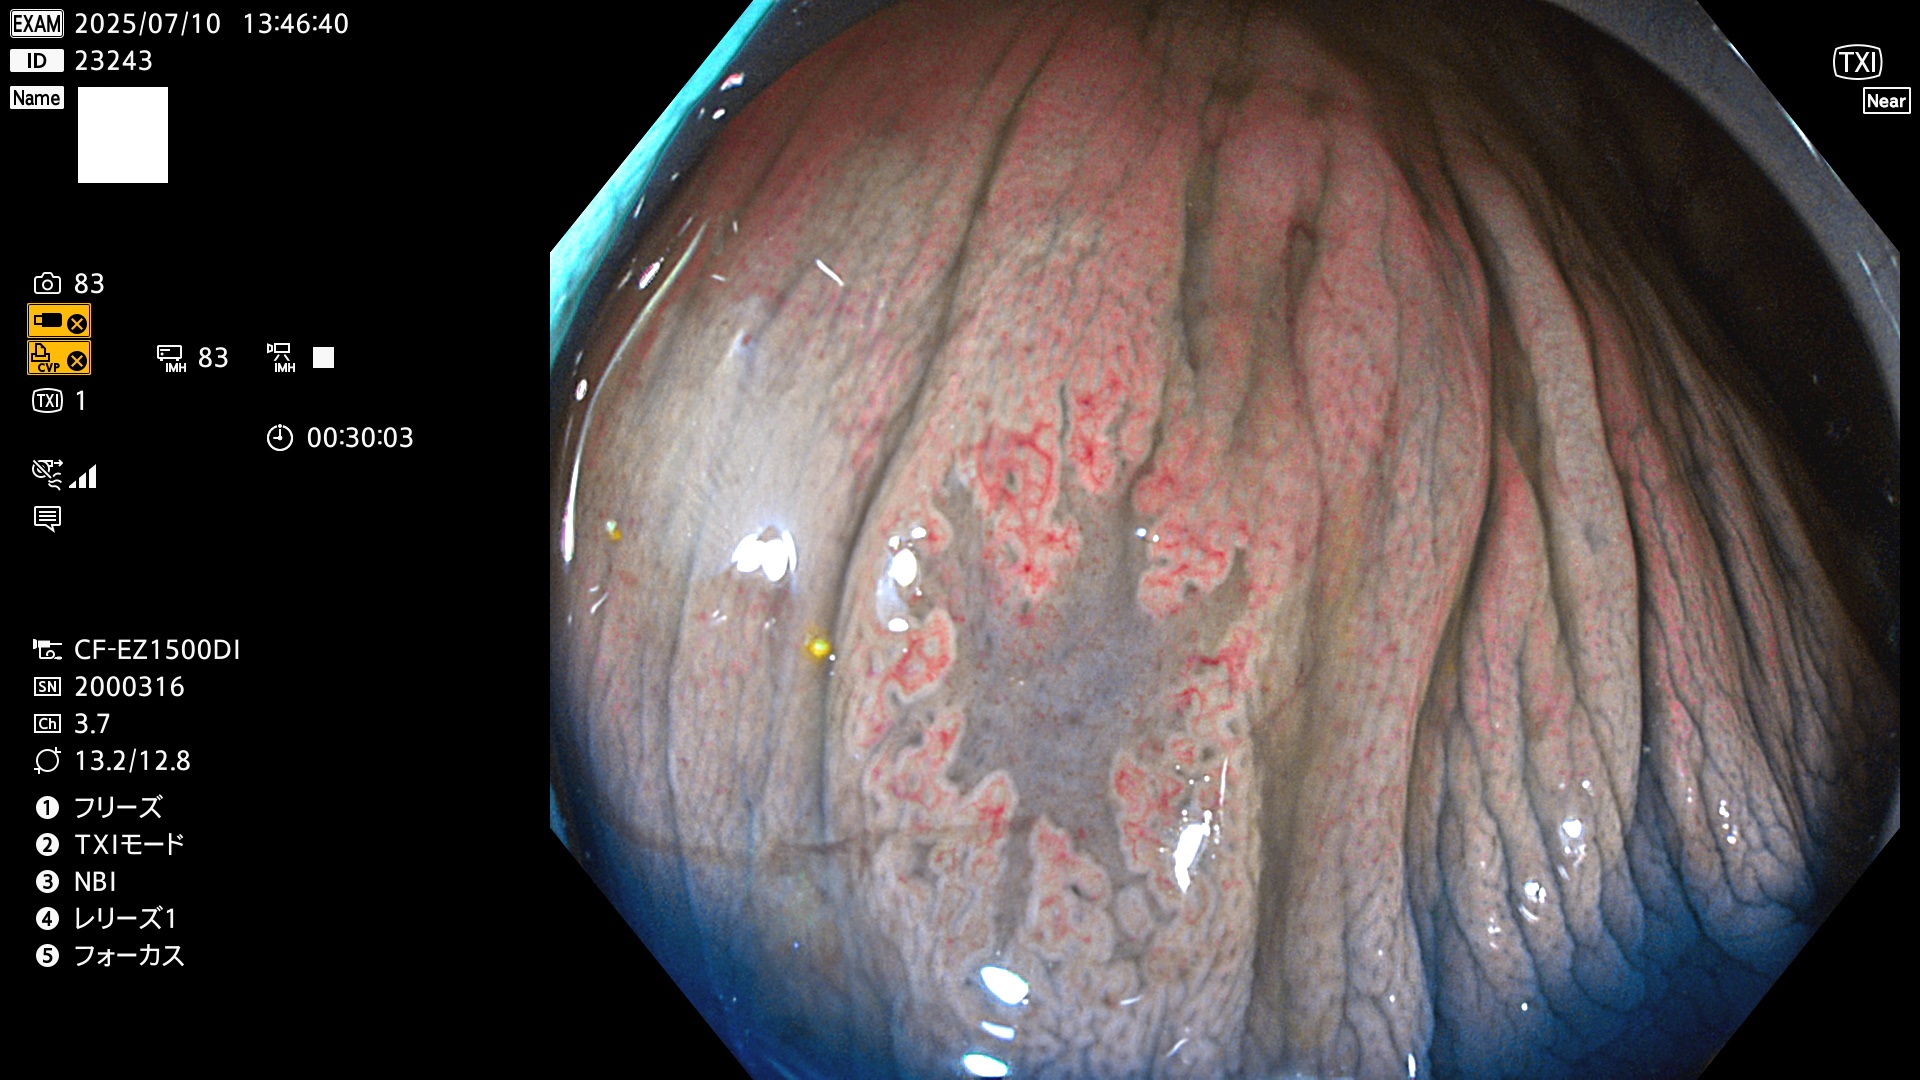

2025年7月10日〜7月13日の4日間(40件)15個 (Uc_ADR=15/40=38%)